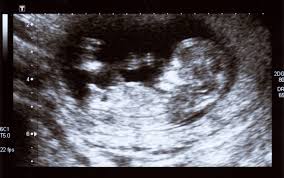

4. 임신 시 태아 초음파 검사

- 태아 상태 확인을 위한 복부 초음파는 임신 중기(20주 전후) 이후 정기적으로 진행